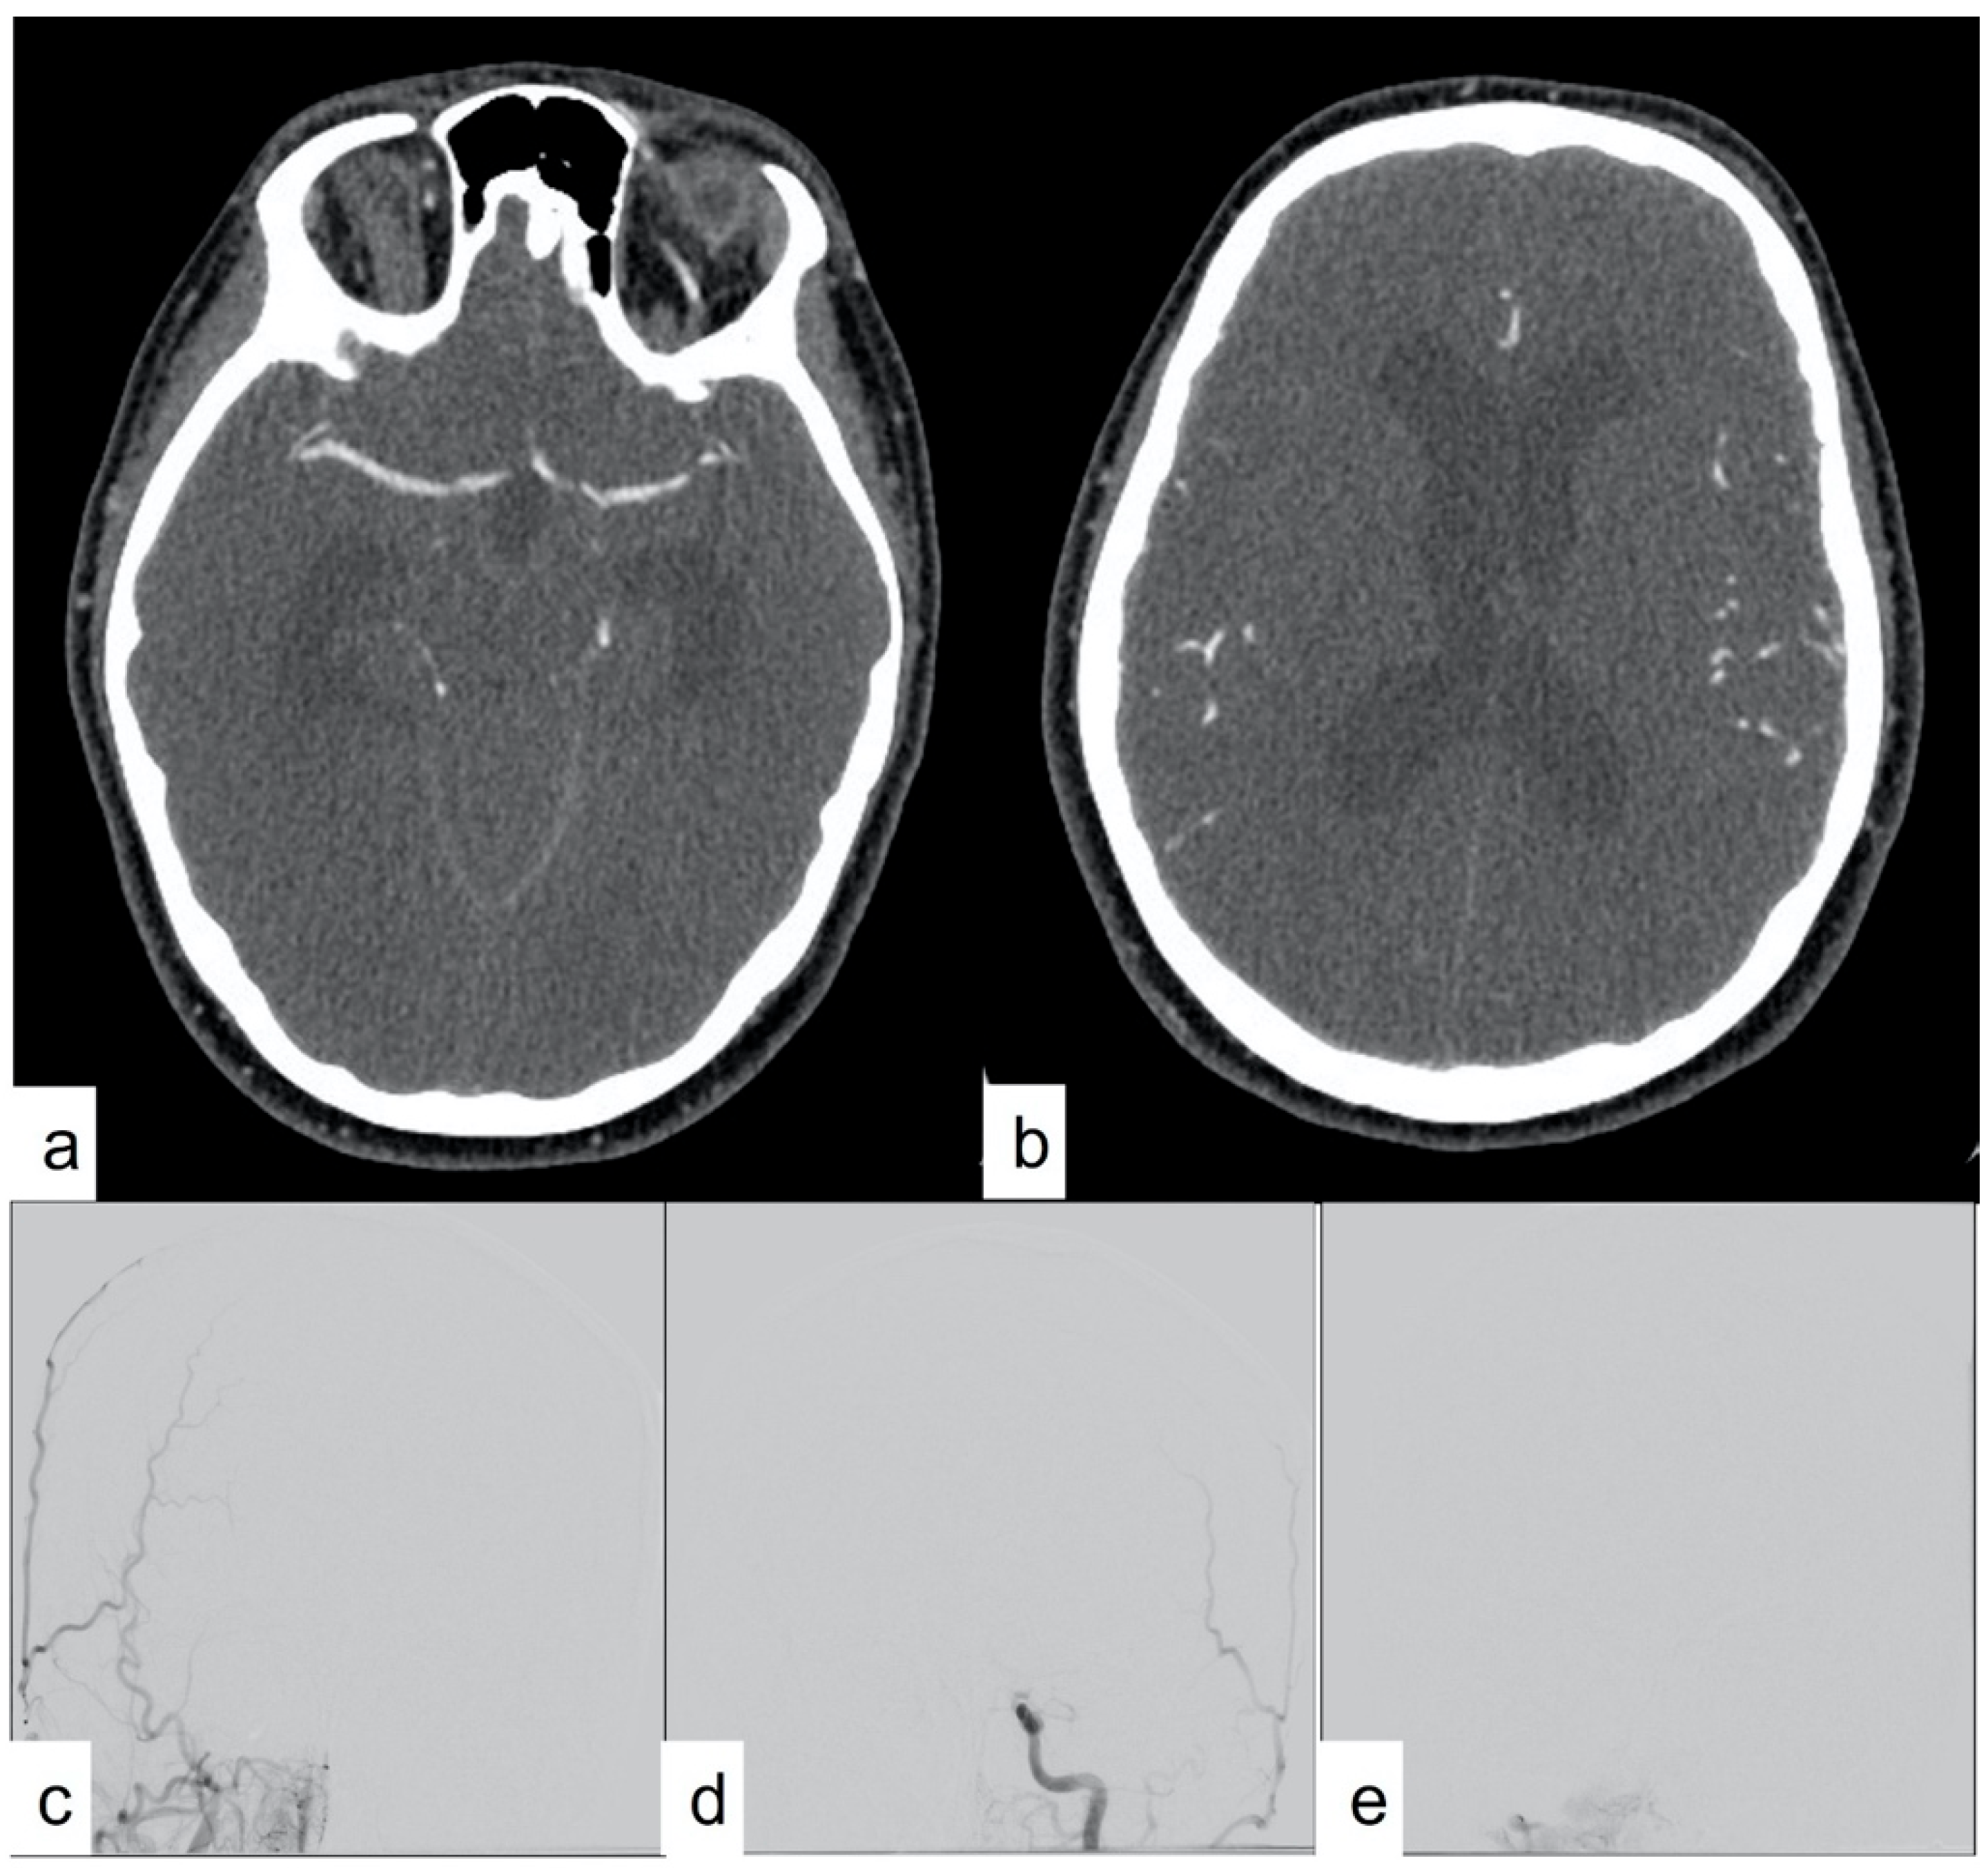

Figure 1. CTA showing classic imaging findings for confirmation of DNC with no opacification of intracranial internal carotid arteries (short arrows) and continued opacification of external carotid branches (long arrows).

CTA has also garnered interest as a method for diagnosing DNC, primarily due to its feasibility, wide availability, non-invasiveness, relatively low cost, and expeditiousness [1,15]. Studies from across the world have reported the efficacy of using CTA for DNC diagnosis. Various imaging protocols and assessment criteria have been described for DNC determination. These protocols are based on the principle of non-opacification of intracranial arteries and veins by the CT contrast in cases of DNC (Figure 1). The utilization of CTA as a supplementary imaging modality rests on the fundamental premise that cerebral blood flow is critical for brain tissue viability, with the presence of blood flow within major intracranial vessels serving as a surrogate marker for viable neurons. However, the absence of blood flow could persist at a later stage due to a lack of metabolic demand, although this area of inquiry remains inadequately explored. A diagnosis of DNC using CTA assumes the uniform global death of brain cells in patients with DNC, and DNC can only be diagnosed when there is a global absence of blood flow in the brain blood vessels. Absence of blood flow only in a small part of the brain, as in cases of ischemic stroke, should not be considered DNC. Any presence of intracranial blood flow, especially in the distal arterial system and venous system, precludes the diagnosis of DNC.